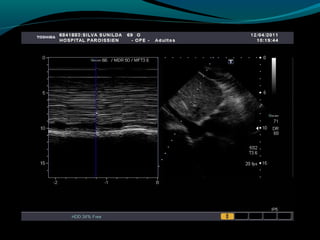

Hipotensión , normotensión, «hipertensión» Tipos de

Ecocardiográficos

SHOCK CARDIOGENICOSHOCK CARDIOGENICO

 ECOCARDIOGRAMA: de elección :

(motilidad parietal, función VI, VD, ruptura

cardíaca, CIV, infarto VD)

Hipotensión , normotensión,«hipertensión» Tipos de Shock Fisiopatología y manifestaciones clínicas y hallazgos Ecocardiográficos